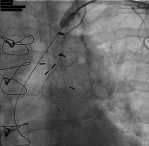

Successful Subclavian Intervention – Pictorial

For illustrative purposes, Figures 4-6 show successful stent placement in a patient with left subclavian stenosis.